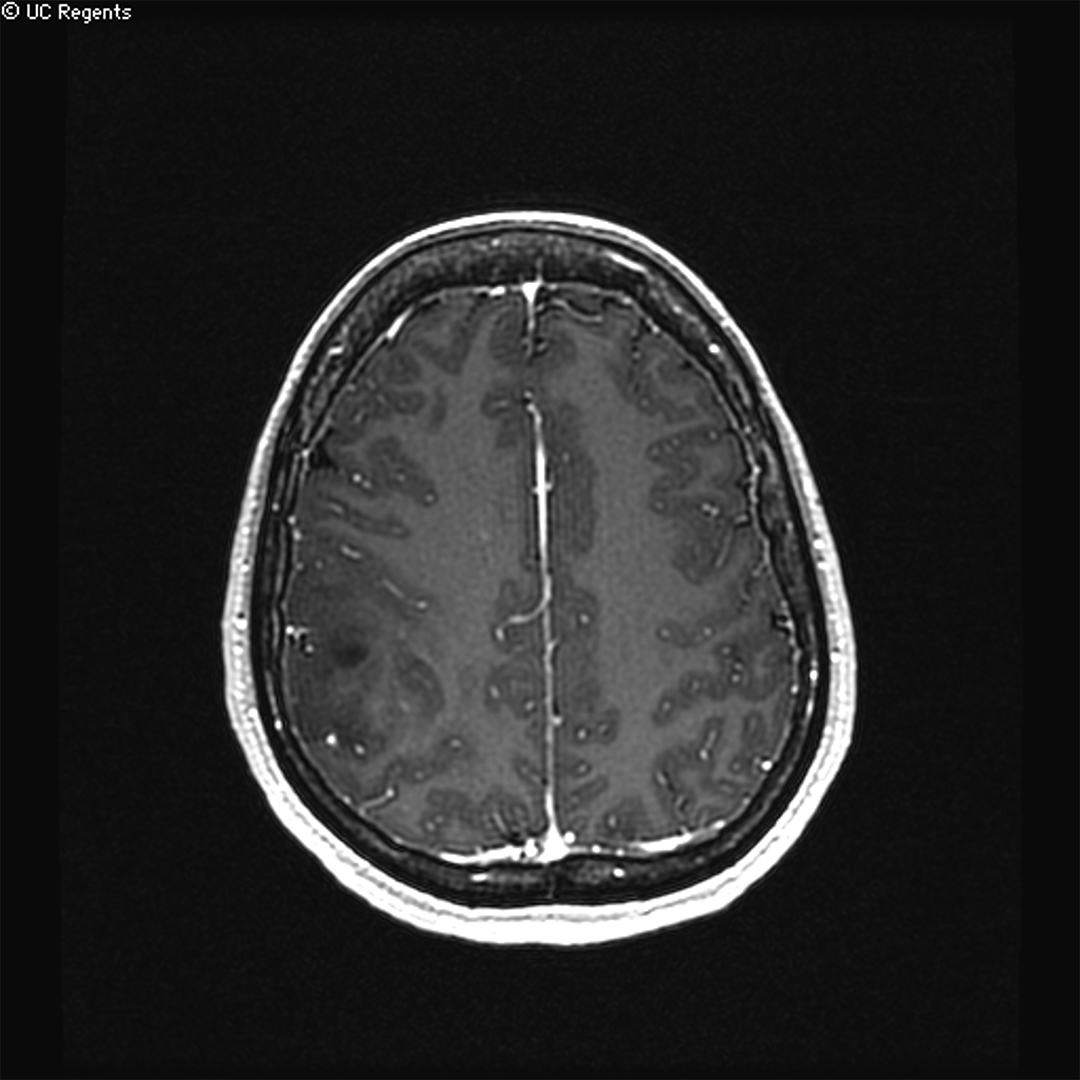

MRI showing a low-grade glioma